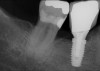

Fig 23. Implant inserted in a regenerated ridge after 6 months healing.

Figure 23

Fig 24. Cone beam scan demonstrating bone circumferentially around the dental implant.

Figure 24

Fig 25. Radiograph showing appearance of restored implant after 1 year.

Figure 25